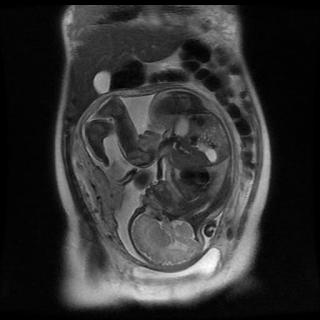

МРТ при беременности

Так как с каждым днем технологии МРТ дают врачам медицинских центров СПб все больший спектр диагностических возможностей, её начинают активно применять в педиатрии, пренатальной диагностике у беременных женщин и онкологии. Как только женщина узнаёт, что станет матерью, у неё сразу возникает вопрос, какие процедуры ей можно делать, а какие противопоказаны. Почти все беременные женщины знают, что им категорически запрещается делать рентген и можно проходить УЗИ.